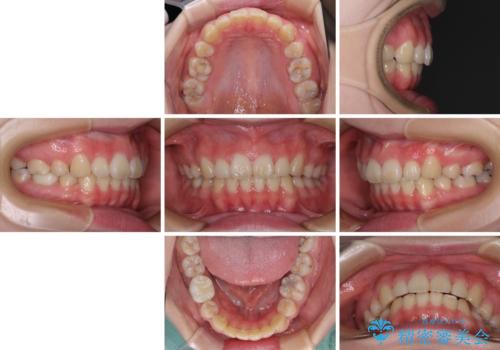

- 口元の突出感を気にして来院された患者様です。

上下左右の第一小臼歯4本を抜歯して口元を下げる治療計画としました。

目立たない装置が希望であったため、上顎が裏側装置である、ハーフリンガル装置を選択されました。

非常に大きな虫歯のあった下顎大臼歯は、根管治療を行い、矯正治療後にオールセラミッククラウンにて補綴治療を行いました。

当初予定では3年以上かかるとお伝えしておりましたが、スムーズに歯列が整い、2年強で終了することができました。